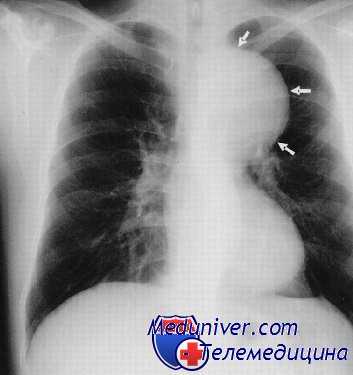

Расширение тени средостения на обзорном снимке влево в области аорто-пульмонального окна, в области талии сердца и при томографическом исследовании прекрасно виден конгламерат увеличенных лимфатических узлов, которые располагаются в переднем средостении. Объемные образования, которые состоят из множества лимфатических узлов, отличают такой процесс от обычных опухолей средостений.

С другой стороны, эти лимфатические узлы могут вырастать в патологическое образование, которое совершенно неотличимо ни от каких других опухолей средостений, с признаками инвазии, с вовлечением в грудной стенке, со сдавлением крупных сосудов, со стеснением и сужением трахеи главных бронхов.